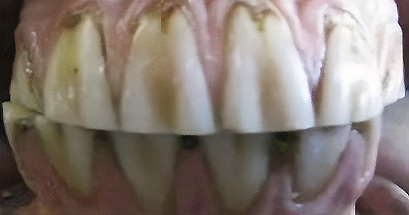

Crib biters (Figure 1b) cause considerable abnormal wear to the occlusal and rostral surfaces of their incisors. These horses are at a higher risk of developing colic during their lifetime (a 35% chance), with epiploic foramen entrapments 72 times more likely to occur.